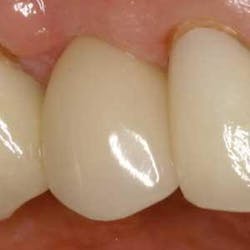

Figure 21 - Three-week postop view, facial closeup. Note the papilla development and soft-tissue architecture at three weeks postop. The implant-abutment-crown unit has integrated nicely.